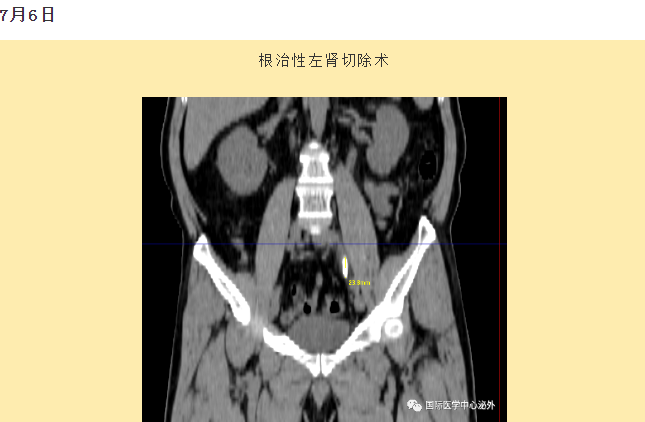

西安國際醫(yī)學中心醫(yī)院順利完成了達芬奇Xi(第四代)機器人裝機。7月6日—7月15日,泌尿外科成功完成了達芬奇Xi(第四代)機器人手術(shù)6例,標志著科室微創(chuàng)外科邁入新時代,造福萬千患者。